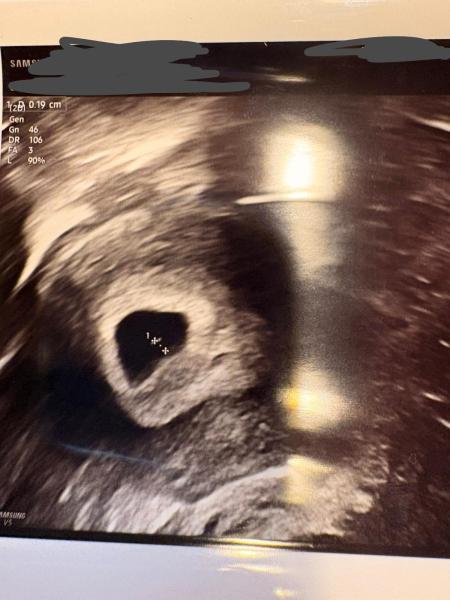

Hallo liebe Jasy,  letzte Woche Mittwoch war ich wieder beim Arzt da ich leichte Blutungen hatte wegen einem Hamatom. Soweit ist alles gut. Ich hab auch ein neues Foto bekommen. Ich füge es mal bei. Übermorgen habe ich wieder einen Termin zur Kontrolle. Ich hoffe sehr, dass man dann auch schon das Baby sehen kann und vielleicht auch schon den Herzschlag.  Bisher ist die Fruchthöhle mit dem Dottersack zu sehen.   Liebe Grüße ☺️

Bild zu